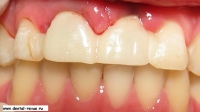

3. Вид до операции.

24. Временные коронки после установки.

25. Временные коронки после установки.

26. Временные коронки сразу после установки при сомкнутых зубах.

27. Улыбка пациента после установки временных коронок.